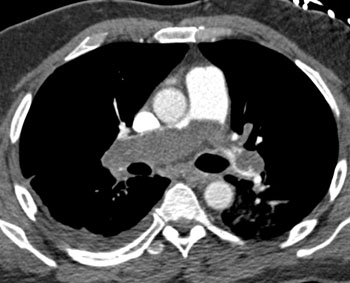

|  | Question 13: A 55 year old man with past medical history of pulmonary hypertension, systemic hypertension, and hyperlipidemia presented with dyspnea. A contrast enhanced computed tomography (CT) scan revealed bilateral pulmonary emboli. Patient was started on anticoagulation and discharged home uneventfully. A repeat CT weeks later suggests? |